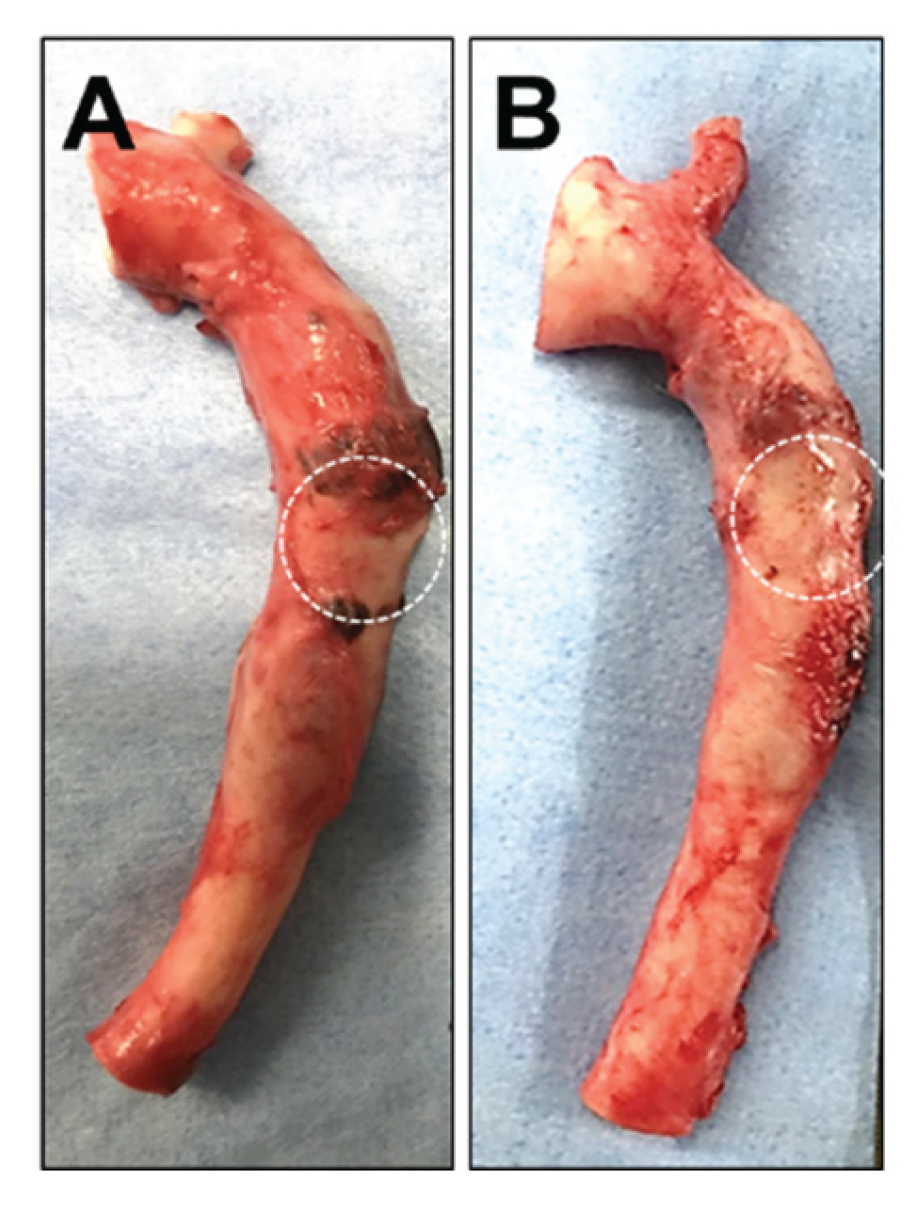

Two weeks after the administration of either saline or the HMSC fiber, the thoracic aorta specimens were harvested and grossly examined. No significant macroscopic differences were observed in the aneurysm region between the two intervention groups (Figure 7A, 7B), indicating that any potential effects of the interventions were not readily detectable by gross inspection at this time point.

Representative gross images of thoracic aorta specimens transplanted into the aneurysm model without (A) or with (B) HMSC fiber administration. The dashed circles indicate the aneurysm region.